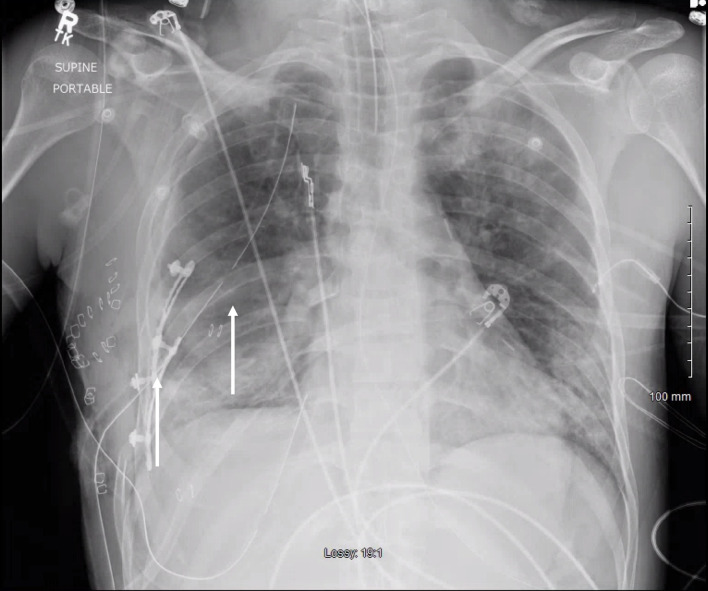

对于多发性肋骨骨折或胸部外翻的患者来说,肋骨固定是一种值得推荐的干预措施,可改善呼吸急促、显著减轻疼痛并缩短住院时间。在此,我们报告了一名胸内肋骨固定术后出现肺水肿患者的独特且极其罕见的发现。一名有酗酒史的 32 岁男性在一次车祸后被送往急诊科创伤室。计算机断层扫描(CT)显示患者右侧血气胸,第四至第九根肋骨骨折并移位。随后使用钛合金 RibFix 固定桥对右侧第五和第六根肋骨进行了固定,并沿肋骨后表面植入胸腔内。术后第 11 天,患者出现肺水肿,在 CT 引导下将引流导管置入积水处。患者接受了为期 3 天的组织浆肌酶原激活剂(tPA)和 DNase 治疗。术后第 15 天,复查 CT 扫描显示,患者的肺水肿明显好转,有证据表明脓肿已经消退。总共 7 天后,患者停用了抗生素,并于术后第 20 天出院。本病例报告为胸腔内肋骨固定术并发症的处理提供了信息。

Rib plating is a recommended intervention for patients with multiple rib fractures or flail chest to improve shortness of breath, significantly reduce pain, and shorten the length of hospital stay. Here, we report a unique and extremely rare finding in a patient with empyema following intrathoracic rib fixation. A 32-year-old male with a history of alcohol use disorder presented to the emergency department trauma bay after a motor vehicle accident. Computed tomography (CT) showed right hemopneumothorax and fourth to ninth rib fractures with displacement. The right fifth and sixth ribs were then plated using a titanium RibFix bridge, implanted intrathoracically along the posterior surface of the ribs. On postoperative day 11, the patient developed an empyema and a CT-guided drainage catheter was placed into the collection. The patient was given a 3-day course of tissue plasminogen activator (tPA) and DNase for the treatment of his empyema. On postoperative day 15, a repeat CT scan demonstrated significant improvement in the empyema with evidence of abscess resolution. Antibiotics were discontinued after a total of 7 days and the patient was discharged on postoperative day 20. This case report contributes information to the management of complications in intrathoracic rib fixation.